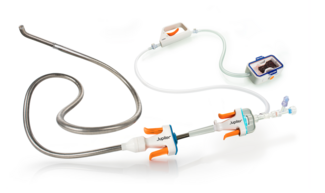

We describe a case of a 60-year-old female who was referred for cardiac catheterization after an abnormal dobutamine stress echcardiogram for 6 segments of inducible myocardial ischemia in anterior and lateral areas. Right radial artery access was obtained via the modified Seldinger technique and 6 Fr standard short hydrophilic sheath was placed. Initially, a standard 1.5 J 0.035″x180cm Rosen wire (Infiniti Medical, Inc.) was inserted; however, it was difficult to advance. An angiogram showed a radial loop.

We describe a case of a 60-year-old female who was referred for cardiac catheterization after an abnormal dobutamine stress echcardiogram for 6 segments of inducible myocardial ischemia in anterior and lateral areas. Right radial artery access was obtained via the modified Seldinger technique and 6 Fr standard short hydrophilic sheath was placed. Initially, a standard 1.5 J 0.035″x180cm Rosen wire (Infiniti Medical, Inc.) was inserted; however, it was difficult to advance. An angiogram showed a radial loop.

The loop was successfully negotiated with a 0.035″x 150cm Glidewire (Terumo Medical Corp.). A 5 Fr JR4 catheter was passed over the wire and used to straighten the loop. Next, the Glidewire was exchanged for a Rosen wire. The JR4 catheter was removed and the short sheath was exchanged for a 35cm 6 Fr hydrophilic sheath. The procedure was successfully completed. The patient had no pain or complication noted either during or after the procedure. In addition, vascular complications and arterial spasm were successfully avoided.

The loop was successfully negotiated with a 0.035″x 150cm Glidewire (Terumo Medical Corp.). A 5 Fr JR4 catheter was passed over the wire and used to straighten the loop. Next, the Glidewire was exchanged for a Rosen wire. The JR4 catheter was removed and the short sheath was exchanged for a 35cm 6 Fr hydrophilic sheath. The procedure was successfully completed. The patient had no pain or complication noted either during or after the procedure. In addition, vascular complications and arterial spasm were successfully avoided.

Transradial cardiac catheterization is an exciting technique that has many advantages over the traditional femoral approach. Most importantly it is a safe option for PCI with potential same day discharge for uncomplicated cases. Despite its advantages, some challenges may be encountered with the transradial approach. After arterial access and spasm, vascular artery anomalies constitute a significant number of procedural failure. Radial artery anomalies are encountered in greater than 17% of cases performed in literature. Of note, radial loop accounts for up to 16% of these anomalies. Furthermore, they account for high percentage of procedural failure. Other authors have suggested using hydrophilic wire to cross the loop, and then advancing catheters over this. In our institution, we use a standard Rosen wire which has a smaller J tip and can pass more easily than standard guidewires. In our case, we had difficulty traversing the radial loop with the Rosen wire. However, we were able to cross the loop. Initially, we used a hydrophilic wire (Glidewire, Terumo) to cross the loop and a 5Fr JR4 catheter to straighten it. However, in our experience exchanging the short sheath for a long hydrophilic sheath allows other bulkier catheters to cross easily. Therefore, we suggest that when a radial loop is encountered, a hydrophilic wire can be used to cross the loop. If the hydrophilic wire fails then a 0.014″ coronary wire can be used. A JR 4 catheter can be used to straighten the loop, however, if that is difficult then a hydrophilic catheter can be used. After successful negotiation, it is optimal to exchange the short sheath for a longer one, thus making interventions with bulkier catheters beyond the bend feasible, more safe, and successful. If these steps fail, transulnar approach can be used as a bailout. Currently, we are collecting data in our institution for a case series on transradial PCI.

Transradial cardiac catheterization is an exciting technique that has many advantages over the traditional femoral approach. Most importantly it is a safe option for PCI with potential same day discharge for uncomplicated cases. Despite its advantages, some challenges may be encountered with the transradial approach. After arterial access and spasm, vascular artery anomalies constitute a significant number of procedural failure. Radial artery anomalies are encountered in greater than 17% of cases performed in literature. Of note, radial loop accounts for up to 16% of these anomalies. Furthermore, they account for high percentage of procedural failure. Other authors have suggested using hydrophilic wire to cross the loop, and then advancing catheters over this. In our institution, we use a standard Rosen wire which has a smaller J tip and can pass more easily than standard guidewires. In our case, we had difficulty traversing the radial loop with the Rosen wire. However, we were able to cross the loop. Initially, we used a hydrophilic wire (Glidewire, Terumo) to cross the loop and a 5Fr JR4 catheter to straighten it. However, in our experience exchanging the short sheath for a long hydrophilic sheath allows other bulkier catheters to cross easily. Therefore, we suggest that when a radial loop is encountered, a hydrophilic wire can be used to cross the loop. If the hydrophilic wire fails then a 0.014″ coronary wire can be used. A JR 4 catheter can be used to straighten the loop, however, if that is difficult then a hydrophilic catheter can be used. After successful negotiation, it is optimal to exchange the short sheath for a longer one, thus making interventions with bulkier catheters beyond the bend feasible, more safe, and successful. If these steps fail, transulnar approach can be used as a bailout. Currently, we are collecting data in our institution for a case series on transradial PCI.